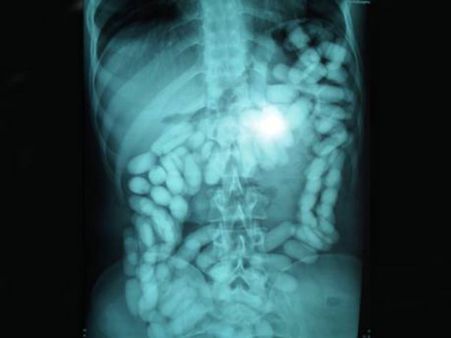

52 કેપ્સ્યુલ

એક નાઇઝિરીયન માણસને મલેશિયાના એરપોર્ટ પરથી જ્યારે પકડવામાં આવ્યો ત્યારે તેના પેટમાંથી 52 ડ્રગ્સની કેપ્સ્યુલ મળી. જે ખરેખરમાં જ મોટી માત્રામાં હતી.